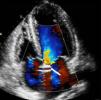

Mulher de 67 anos, com antecedentes de esclerodermia e hipertensão arterial, sem sintomas cardíacos prévios, foi internada para avaliação do envolvimento sistémico da esclerodermia. Ao exame objetivo apresentava um sopro sistólico no apex grau ii/vi. O eletrocardiograma revelou ritmo sinusal e bloqueio fascicular anterior esquerdo. O ecocardiograma mostrou na incidência para-esternal esquerda eixo longo uma imagem tubular anómala em continuidade com a parede anterior da aorta ascendente (Figura 1). Em para-esternal eixo curto a nível da aorta é visível a mesma estrutura tubular circundando a aorta (Figura 2). Em apical quatro câmaras observou-se a imagem tubular com 2mm de diâmetro com 42mm de comprimento, transversal ao septo interauricular. Não foram identificados a origem e o fim da estrutura. Com Doppler de cor observou-se fluxo no seu interior (Figuras 3 e 4). Pelo facto de se suspeitar de uma estrutura vascular, realizou-se cateterismo cardíaco, que revelou uma origem anómala da artéria coronária esquerda (ACE) a partir do segmento proximal da coronária direita com trajeto epicárdico e anterior à aorta (Figura 5). Os achados ecocardiográficos mais associados à esclerodermia são a hipertensão pulmonar e o envolvimento pericárdico incluindo a pericardite fibrinosa. Não há casos descritos da associação entre esclerodermia e origem anómala das artérias coronárias, pelo que este caso poder-se-á tratar de uma coincidência. A origem da ACE a partir do óstio da coronária direita ocorre em apenas 0,15%1 da população, estando associada a morte súbita2.